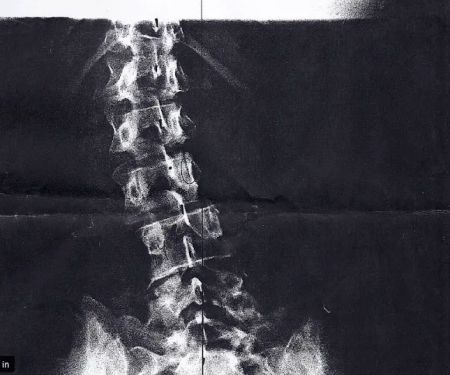

Chiropractic care is a holistic, non-invasive approach to health that focuses on the body's natural ability to heal itself. At its core, it's about addressing the root cause of pain and discomfort, often stemming from misalignments in the spine and musculoskeletal system. Sager Scott DC embodies this philosophy, offering a professional, friendly, and patient-centered environment where your health goals are the top priority. They believe in creating personalized treatment plans that not only relieve immediate symptoms but also promote long-term health and well-being. This is not a one-size-fits-all approach; it’s about understanding your unique body and needs to provide the most effective care possible.

- Spinal Adjustments: The core of chiropractic care, these adjustments aim to correct subluxations (misalignments) in the spine. By restoring proper alignment, this can alleviate nerve pressure, reduce pain, and improve overall body function. Techniques used are gentle, precise, and tailored to the patient's comfort level.

- Treatment for Back and Neck Pain: Whether the pain is acute (from a recent injury) or chronic (long-standing), Sager Scott DC provides targeted care. This includes manual adjustments, soft tissue therapy, and corrective exercises to relieve discomfort and restore mobility.